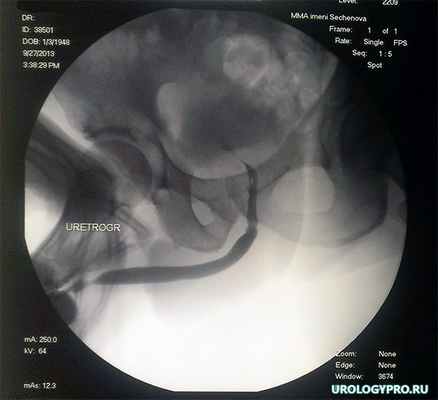

На рис. 5 представлены результаты ретроградной уретрографии через 2 недели после операции и удаления уретрального катетера.

Рис 5. Ретроградная уретрограмма. В зон анастомоза определяется незначительная неровность контуров уретры, сужения нет.